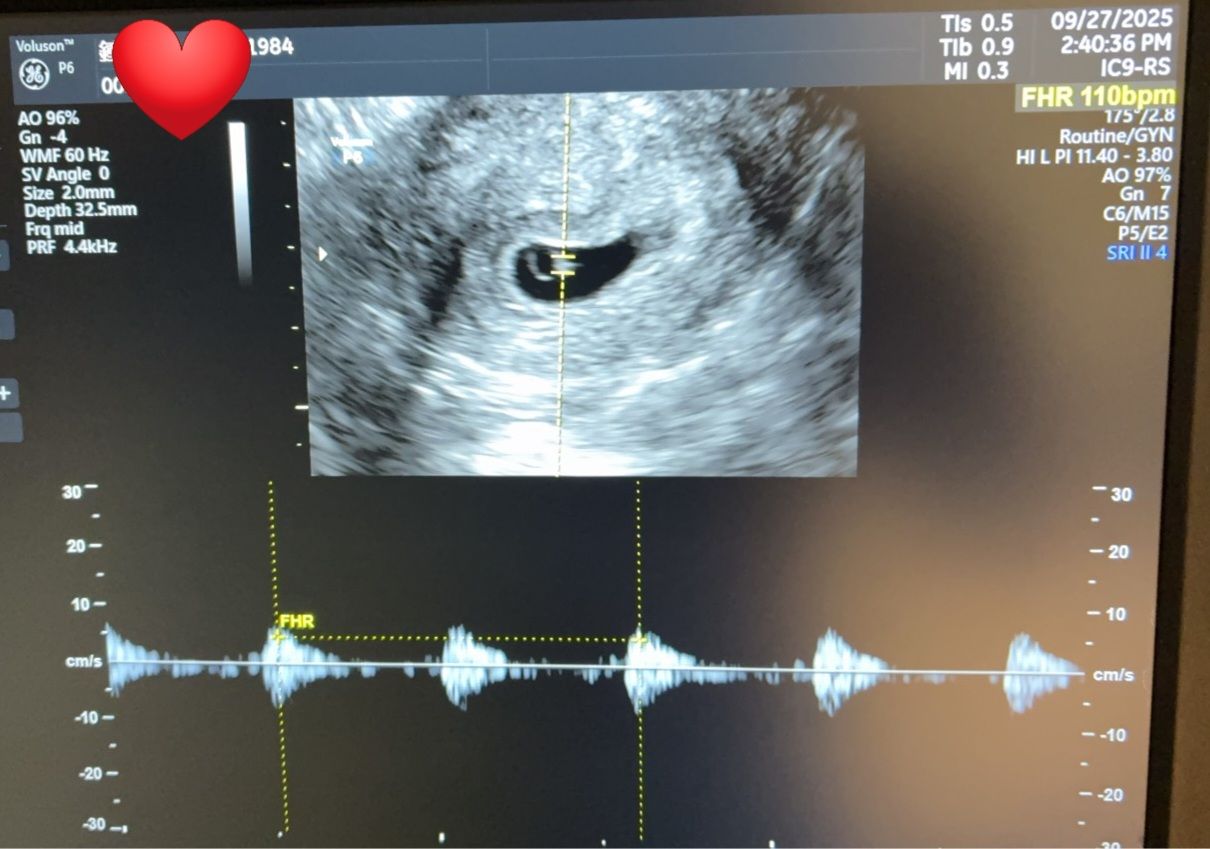

如今,鍾小姐已順利懷孕6週,超音波中清楚可見規律跳動的胎心音,那一刻,不只是感動,更是希望的實現。這份得來不易的生命奇蹟,讓人由衷感謝醫療的用心與不放棄的信念。